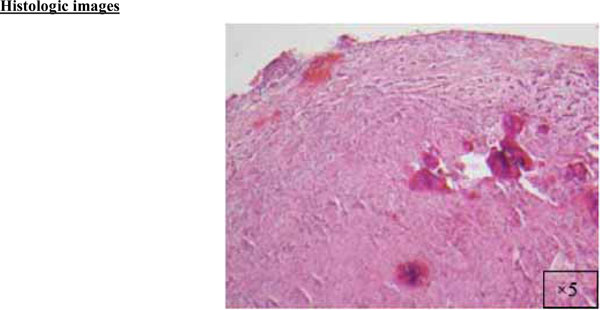

Fig. (2a).

A cellular fibroblastic connective tissue containing numerous cords and nests of odontogenic epithelium (x5).

The findings and treatment plan were discussed with the patient, who agreed to proceed with treatment. A surgical incisional biopsy specimen (1.3 × 1.1 × 0.2 cm) was obtained, removed, and sent for histopathological evaluation. Images from the current patient’s biopsy specimens are shown in Figs. (2a-2g). The specimen was made up of a cellular fibroblastic connective tissue containing numerous cords and nests of odontogenic epithelium and dysplastic dentin or cementum-like calcification material. The mass was diagnosed as COF, WHO type, because of the presence of fibrous and epithelial components.

Histologically, COF is defined as a fibroplastic neoplastic lesion that contains inactive odontogenic epithelium and variable quantities of calcified material. COF may be associated with the crown of an included tooth or the roots of erupted teeth. The maxilla shows a predilection for the front part of the mouth, whereas in the mandible there is a predilection for the posterior regions [1]. Due to its non-exclusive histological features, this lesion may be confused with other entities, such as hyperplastic dental follicles, odontogenic myxomas, and desmoplastic fibromas, highlighting the importance of clinicopathological correlation in the diagnosis of COF [2]. Careful diagnosis is crucial.

There is a wide variety of histologic appearances, ranging from densely hyalinized and cellular, to loose and myxomatous, to nearly acellular (see Fig. 2). Delicate collagen fibers are occasionally identified, along with fibromyxoid stroma. It is this variation that has resulted in the historical separation of COF into two types: the epithelium-poor type (formally referred to as the simple type) or the epithelium-rich type (formally referred to as the WHO type). Features of odontogenic fibromas include inactive-looking odontogenic epithelium that, when present, may appear proliferative or form irregular islands and cords. Calcifications may or may not be present, simulating cementum, osteoid, or dentin. A rare granular cell odontogenic fibroma variant also exists [8].